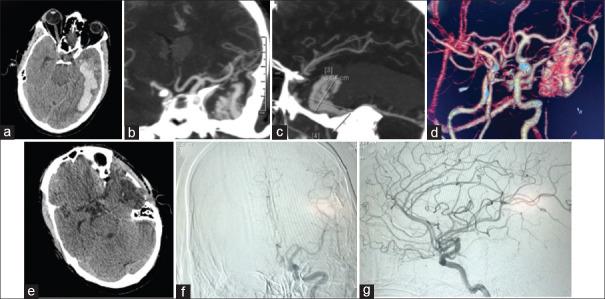

Demographic data, arteriovenous malformation characteristics, and treatment outcomes were evaluated in 43 bAVMs treated with microsurgery between 2009 and 2019. For this series, 43 patients were retrospectively reviewed. A subgroup analysis for Spetzler-Martin grades (SMG) I/II, III, IV/V and III-V were performed. The mRS was used to assess functional outcomes.

Overall, mean age at diagnosis was 33 years (standard deviation = 19). Transient deficit, mRS deterioration and impaired functional outcome occurred less frequently in SMG I-II patients compared with Grade III-V patients combined (29% vs. 32% respectively, = 0.00). All patients with SMG Grade I, Supplemented SMG Grade 2, 3, 4 and 6 had a mRS score of 2 or less at the last follow-up. Age was the only significant predictor of overall outcome after bAVM surgery on Chi-square test ( = 0.046), i.e: all patients <20 years had mRS score of 2 or less on last follow-up. Unfavorable outcome (mRS score of 3 or more than 3) level increased with higher grades in SMG on long term follow-up.

The results of our case series of bAVM with SMG Grade I and Suplemented Grade 2, 3, 4 and even higher grade i.e., 6 can have excellent overall outcome after microsurgical resection. Association of factors which increases the grading system of bAVM like eloquence, deep venous drainage and increasing sizes did not correlate with the predicted unfavorable outcomes, whereas age of patients was a predictor of overall outcome. Although the small sample size of this study is a limitation, age of patient plays important role on the overall outcome.